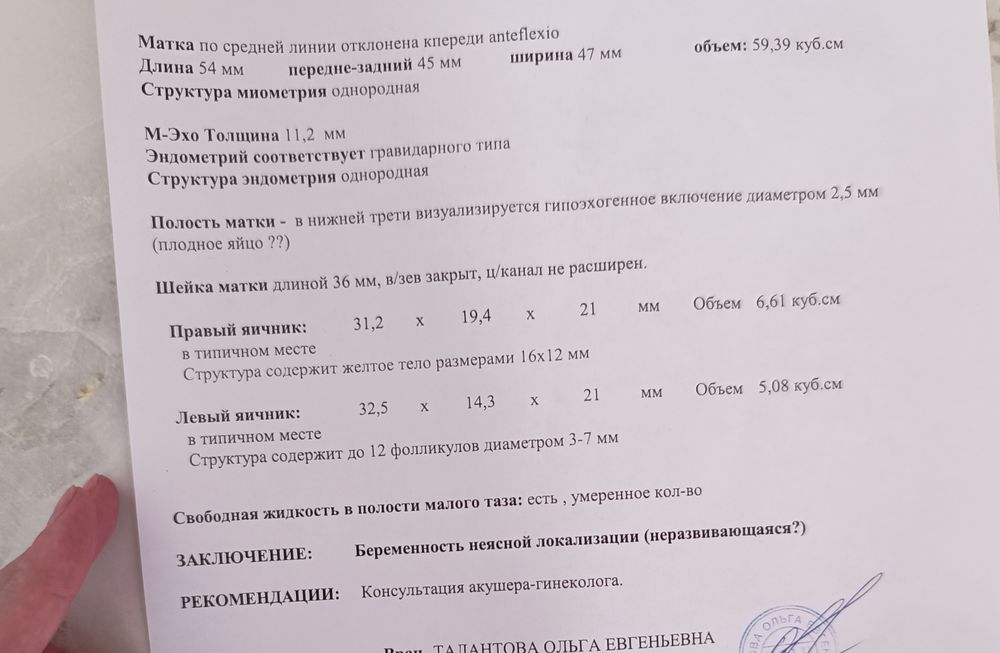

Сходила на УЗИ(хгч вчера 289 встал) , напугали внематочной под ? Сказали есть небольшая жидкость, свидетельствует о внематочной... И мол надо лечь к нам наблюдать 70 тысяч 😡ну как бы не знаю...

Пересдала хгч жду. Похоже на плодное яйцо, сказали мб оно или эндометрий пузырик